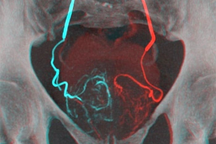

Khối u tuyến tiền liệt khủng của bệnh nhân.

"Khối u tuyến tiền liệt của người bệnh tăng sinh lớn, lên đến 240g, gấp 12 lần khối lượng tuyến tiền liệt bình thường dẫn đến biến chứng sỏi và túi thừa trong bàng quang. Đây là hệ quả của việc ứ trệ nước tiểu và gắng sức rặn tiểu lâu ngày. Nếu không điều trị kịp thời sẽ dẫn đến biến chứng nguy hiểm, có thể đe dọa tính mạng", BS Nguyễn Hồng Long cho biết.